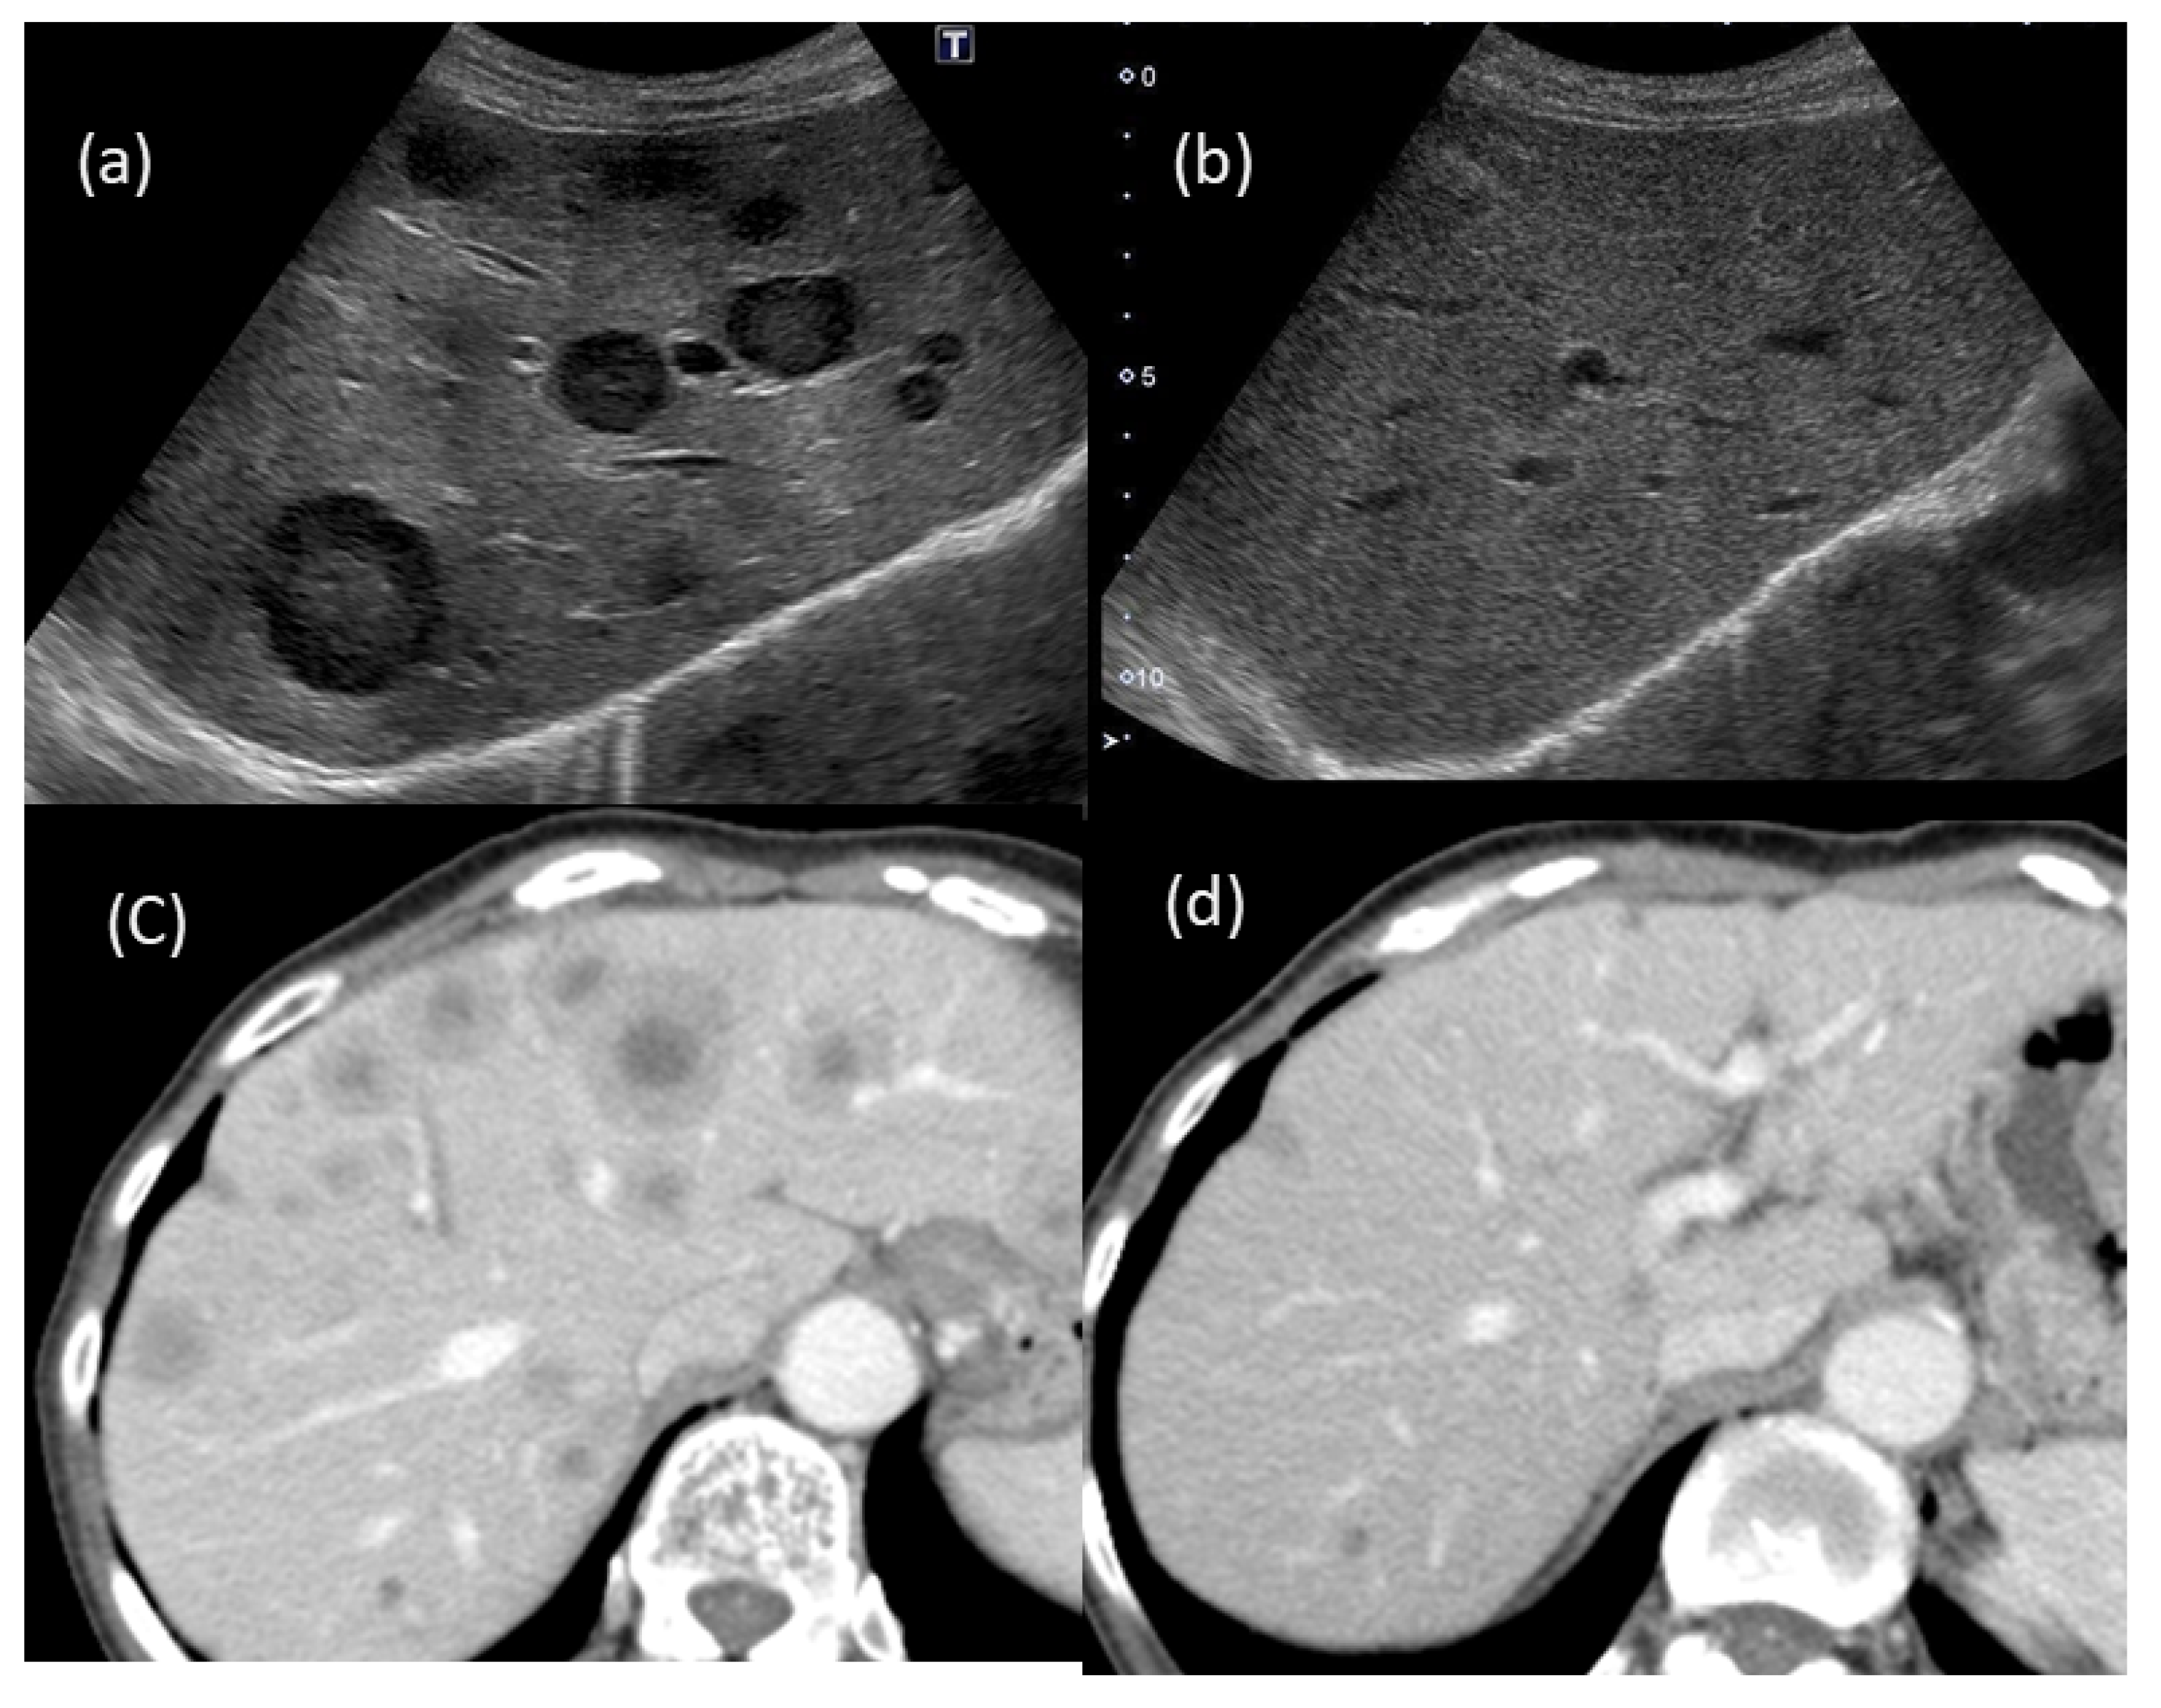

In the US findings (Aplio, Canon Medical Systems, Ohtawara, Tochigi, Japan), a hypoechoic tumor of 10 mm in size was observed (Figure 5a). On the Sonazoid contrast-enhanced US, the tumor showed very slight hypoenhancement in the arterial phase (Figure 5b), washout with peripheral enhancement in the portal phase (Figure 5c) and hypointensity in the Kupffer phase (Figure 5d). A percutaneous liver biopsy showed liver tissue with cell shedding, fibrotic changes, and infiltration of inflammatory cells, including lymphocytes and macrophages. There were no malignant findings. As a result, IPT was thus suggested (Figure 6). After two months of observation, the tumors spontaneously regressed and nearly vanished (Figure 7).

Despite the presence of findings suggestive of metastatic tumors (Figure 1 and Figure 2), we assessed several different types of clinical data available, such as different imaging techniques, and ultimately concluded that the tumors were benign. Thus, it is quite important to make a diagnosis by combining various imaging findings and considering the patient’s background and clinical course.

Figure 7. Changes in the US and CT findings: multiple tumors that had been suggested to be metastatic tumors (a,b) were barely detected after two months of observation; (a,b) US findings; (c,d) CT findings.